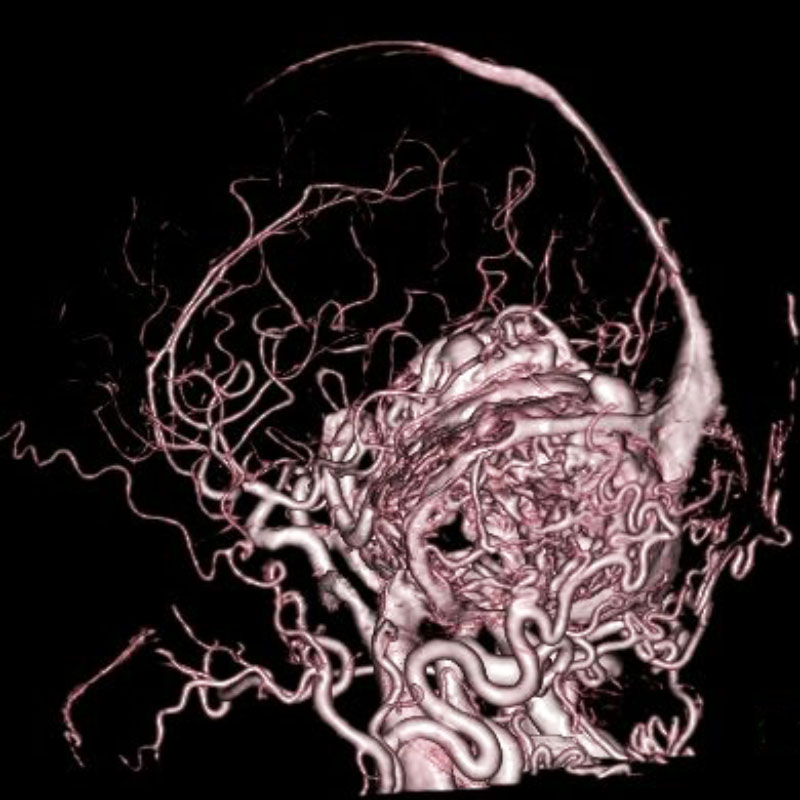

脳動静脈奇形

血管塞栓術

松田/濵田/元永